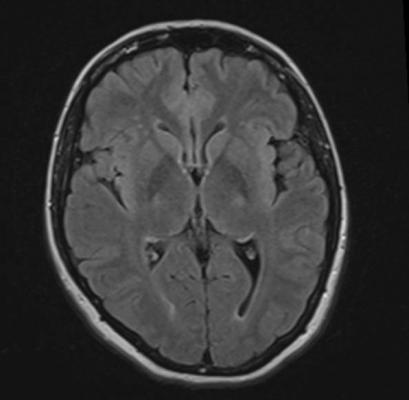

The researchers analyzed structural brain magnetic resonance imaging (MRI) exams in 127 men and women, including 59 people (28 women and 31 men) who were previously dependent on cocaine, amphetamines, and/or methamphetamine for an average of 15.7 years, and 68 healthy people (28 women and 40 men) who were similar in age and gender. The MRI results showed that after an average of 13.5 months of abstinence, women who were previously dependent on stimulants had significantly less gray matter volume in frontal, limbic and temporal regions of the brain.